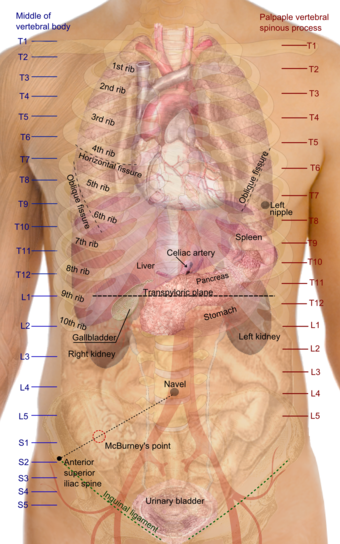

اسقاطات على السطح لأجهزة الجذع، وتبدو فيه منطقة الصدر ممطوطة لأسفل حتى تقريباً نهاية oblique lung fissure خلفياً، ولكن أكثر عمقاً في حدها الأسفل الذي يناظر الحد العلوي للكبد.  | |